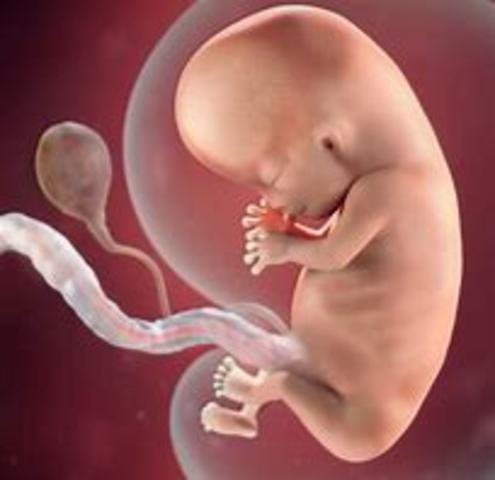

• 3 er mes 9.a - 10. a semanas

3 er mes 9.a - 10. a semanas

El hígado casi esta desarrollado totalmente; aparecen los riñones definitivos y el feto empieza a verter orina en el líquido amniótico. La cara casi constituido, progresivamente, adquiere una forma más «humana»:. Los ojos, que estaban muy separados y situados a cada lado de la cabeza, están ahora de frente, recubiertos por los párpados; se dibujan los labios; y las orejas son como dos pequeñas ranuras. Los miembros se alargan, en especial los brazos.

• 11. a-12.a semanas

Aparecen los primeros huesos. El feto ha empezado a moverse, aunque tan débilmente que la madre todavía no puede notarlo. Se trata de movimientos no relacionados con ningún tipo de estímulo. Sin embargo, gracias al estetoscopio de ultrasonidos, los padres pueden oír los latidos del corazón de su futuro bebé. A lo largo de este mes se diferencian los órganos sexuales: los órganos sexuales masculinos se hacen patentes, no son visibles en la eco grafía.

• 13.a semana

Ya se puede medir la cabeza por medio de ultrasonidos. A partir de esta medición se calcula, con un margen de error de algunos días, el final del embarazo (y por tanto la fecha teórica del parto). El feto mide ahora 12 cm desde la cabeza hasta los talones y pesa 65 g.